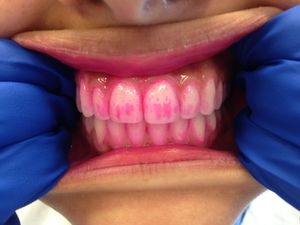

치태는 육안으로 확인하기 어려울 수 있지만, 치태 착색제(검출 젤 또는 정제)를 사용하면 쉽게 확인할 수 있다. 치태 착색제는 치태가 있는 부위를 붉은색 등으로 착색시켜 보여준다.[1]

치태 검출 제품은 검출제라고도 하며, 치태를 임상적으로 볼 수 있게 해준다. 치아의 깨끗한 표면은 검출제를 흡수하지 않고, 거친 표면만 흡수한다. 치태 검출 젤은 가정이나 치과에서 사용할 수 있다. 이러한 제품에 포함될 수 있는 요오드, 식용 색소 또는 기타 성분에 대한 알레르기가 있는지 일반의와 확인하는 것이 필요하다. 이 젤은 치태 바이오필름의 존재를 평가하는 시각적 보조 수단을 제공하며, 치태의 성숙도도 보여줄 수 있다.

치태 착색제는 치태 착색 젤과 유사하지만, 입 안에 넣고 약 1분 동안 씹어 사용한다는 차이점이 있다. 씹고 남은 정제나 침은 뱉어낸다. 착색 젤은 치태의 존재를 보여주지만, 치태의 성숙도 수준은 종종 보여주지 못한다. 치태 착색제는 최적의 세정을 위해 치아를 닦기 전과 후에 사용하도록 교정 장치를 사용하는 환자에게 처방되거나 제공되기도 한다. 또한 어린 아이나 특정 부위의 치태 제거에 어려움을 겪는 환자에게 유용한 교육 도구이기도 하다. 치태 착색 젤과 정제는 모든 연령대의 개인이 효과적인 치태 제거를 보장하는 데 유용하다.